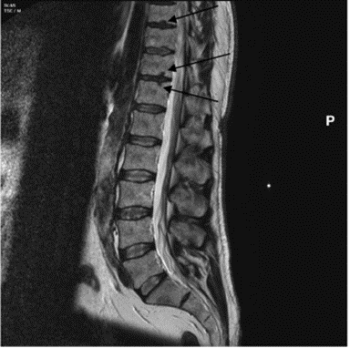

Schmorl’s nodes are depressions on the superior and/or inferior surfaces of the vertebral body (figure 1), due to herniation of the nucleus pulpous through the cartilaginous end plate. They are most common on the lower thoracic (T8-T12) and the upper lumbar vertebrae (L1-L2) (Rogers and Waldron 1995, 27). Schmorl’s nodes are of significant interest in bioarchaeology and have been used to interpret past human health and lifestyle and offer an indication of trauma within a historical population (Üstündağ et al. 2010; Novak et al. 2012). Clinically they are frequently asymptomatic but can cause acute backpain, and thus present a problem in modern populations (Kyere et al. 2012, 2119; Abu-Ghanem et al. 2013). The reported clinical and palaeopathological literature indicates that Schmorl’s nodes prevalence ranges vastly between 5 and 70% (Silberstein et al. 1999, Dar et al. 2010, 672). Comparison between historical populations is difficult due to variation in the methodological approach of assessing Schmorl’s nodes, in addition to a limited understanding of the aetiology of the condition (Matt and Rehman et al. 2014; Trzciński et al. 2017, 301-303). Clinically, magnetic resonance imaging (MRI) (figure 2) is used to assess the number and severity of Schmorl’s nodes in living individuals (Mattei and Rehman 2014, 39). In osteoarchaeology, the pathology is often identified and assessed during post-excavation analysis of past populations via macroscopic techniques.